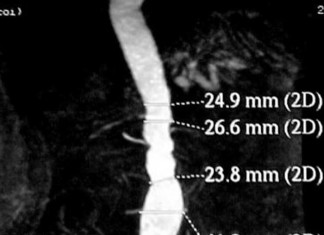

Dieta rica en fruta reduce el riesgo de aneurisma

Comer fruta puede disminuir su riesgo de desarrollar un aneurisma aórtico abdominal, según un estudio grande, de larga duración.

Un aneurisma aórtico abdominal es una...